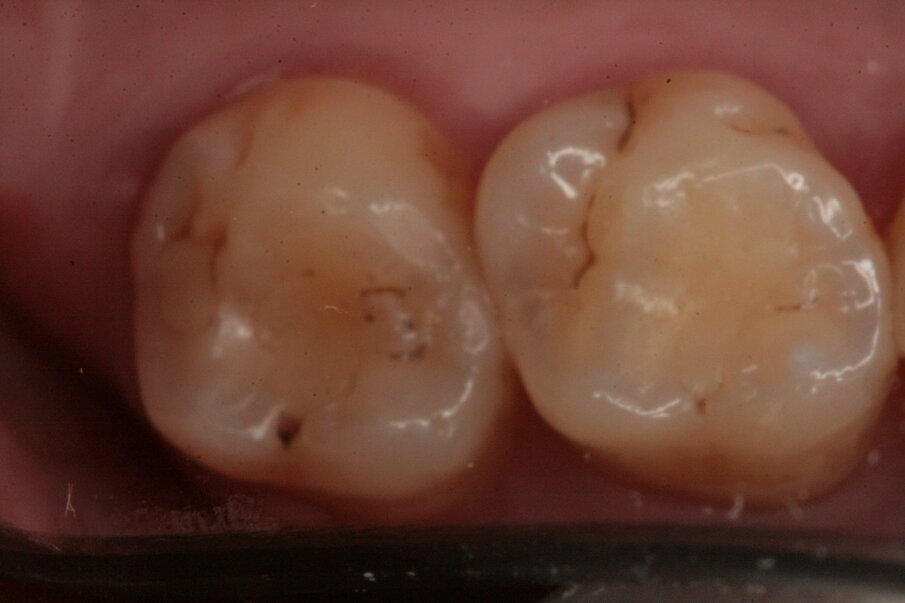

Si è proceduto alla ricostruzione diretta degli elementi 46, 45 e 44 mediante una massa di smalto e una di dentina (Figg. 23-27). L’elemento 47 è stato riabilitato mediante una ricostruzione indiretta in quanto il tessuto dentinale sano residuo era esiguo passando attraverso un build-up pre-protesico per esporre i margini sui quali alloggiare il manufatto (Fig. 28). Il restauro è stato realizzato in resina composita in quanto gli studi longitudinali dimostrano un ottimo follow-up a lungo termine (Fig. 29). La cementazione è avvenuta sempre con isolamento del campo operatorio facendo uso di un cemento duale (Fig. 30).

Fig. 23_Visione occlusale di 46 e 47.

Fig. 27_Restauro effettuato.